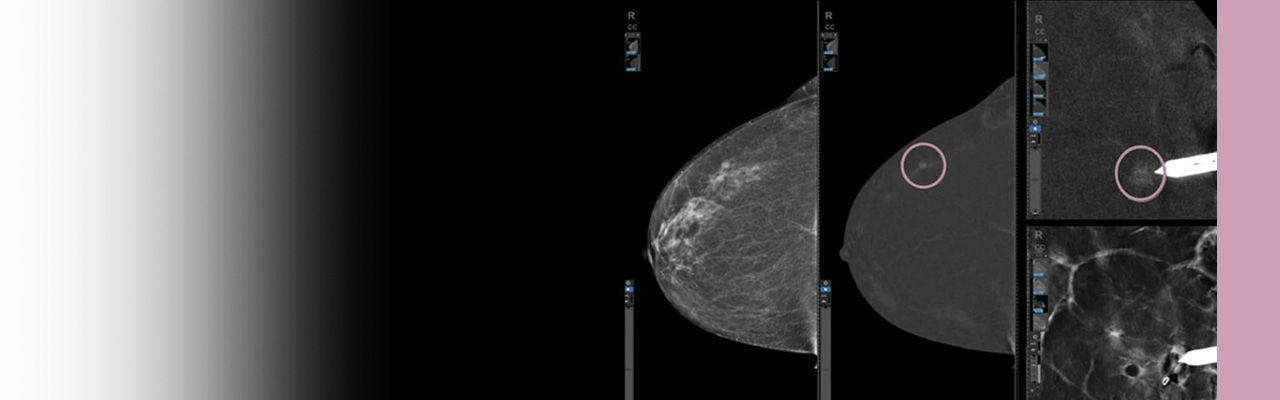

Advanced clinical review & smart tools